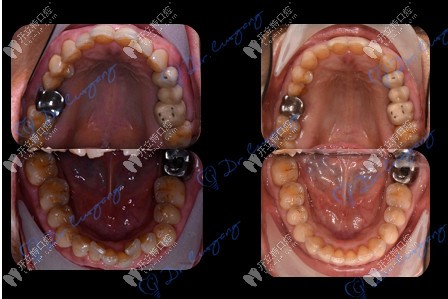

牙齒矯正前后對比

經(jīng)過檢查,王阿姨非常符合牙齒矯正所需的口腔條件。這得益于她幾十年來,堅持在飯后使用牙線、沖牙器來清理食物殘渣,注腔衛(wèi)生,因此牙齒沒有出現(xiàn)松動脫落的現(xiàn)象,牙槽骨情況也十分健康。

歷經(jīng)一年半的佩戴,如今,王阿姨已經(jīng)順利地摘下牙套,牙齒恢復(fù)了整齊,并保持著健康的口腔狀態(tài)。她還經(jīng)常向身邊家人朋友們科普牙齒保健知識,帶動他們關(guān)注口腔健康。